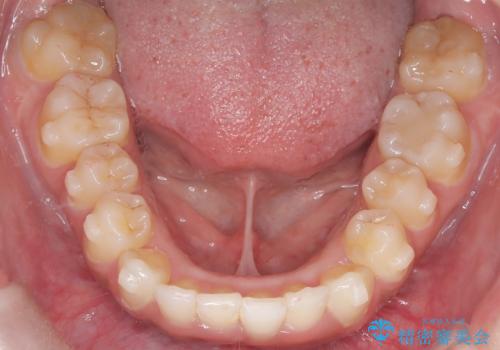

前歯の出っ張りとガタつきを改善

- 「前歯が出ていて並びも悪いのが気になる」との主訴で来院されました。診察の結果、上顎前歯の前突と中等度の叢生(ガタつき)が認められ、歯がきれいに並ぶスペースが不足していました。横顔のバランスと歯並びの両方を整えるため、上顎の左右の第一小臼歯2本を抜歯し、前歯を内側に下げながら歯列全体を整える治療計画を立てました。

患者さんのご希望もあり、取り外しが可能で目立ちにくいインビザライン(マウスピース矯正)を選択。抜歯スペースを活用しながら、叢生と前突感の改善を同時に目指しました。

治療はインビザラインによって進め、抜歯スペースを使って前歯を内側に引き込みながら、歯のガタつきも順に整えていきました。初期の段階で前歯の見た目が大きく変わり、患者さんにも「印象が柔らかくなった」と非常に喜んでいただけました。

しかし、途中で来院が途絶えてしまい、インビザラインのアカウント(治療管理期間)が終了。再発注やリカバリーが難しくなったため、治療再開のためにワイヤー矯正の提案を行いましたが、患者さんのご希望により再治療は見送られることとなりました。

インビザラインは高い効果が期待できる一方、継続的な来院と装着が不可欠な治療法です。継続していればさらに良い結果が得られたと考えられるケースでした。